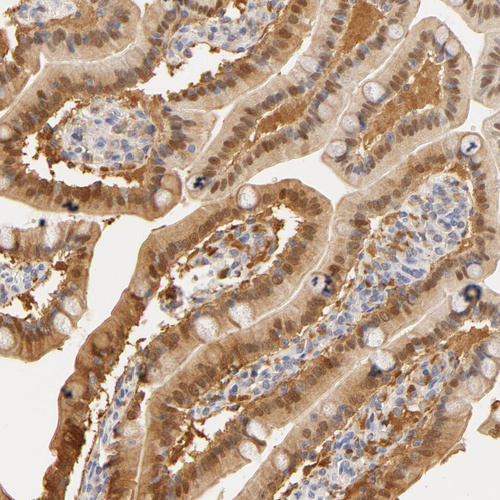

Immunohistochemical staining of human duodenum shows moderate cytoplasmic and nuclear positivity in glandular cells.